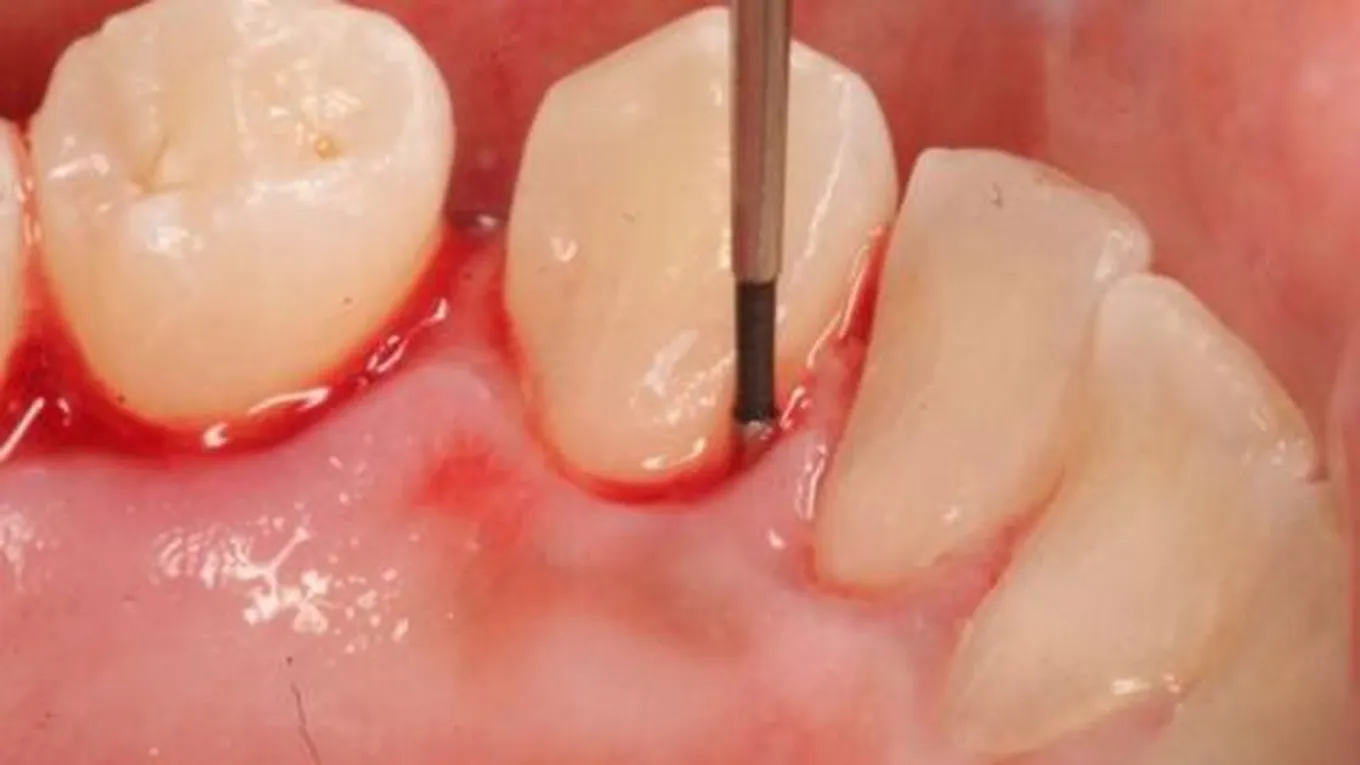

- طبقة لزجة لونها يميل للأبيض وتسمس هذه المادة (الصفائح الدموية) تتعايش هذه البكتيريا على هذه المنطقة وتنمو بطريقة سريعة و تصبح واسعة الإنتشار وذلك لأن هذه الصفائح هي المكان المناسب لنمو مثل هذه البكتيريا التي تسبب التهيج الكبير للثة وبفعل هذا الغلتهاب تصبح منتفخة ومتورمة من بين الأسنان حتى الأسفل وغذا ترك هذا الإلتهاب دون علاج فإنه يزداد مع الوقت ليتخلل إلى داخل اللثة ويصل إلى منبت السن ثم إلى العصب ويدمر ها الإلتهاب العصب السني مما يؤدي إلى فقدان السن بالنهاية.

- نزول الدم أثناء تنظيف الأسنان و تنظيف اللثة.

- نزول الدم عند تناول اي من المواد الغذائية الصلبة مثل التفاح أو أي نوع أخر من الفاكهة، و تحدد نسبة الإلتهاب بالفم على قدر النزيف.